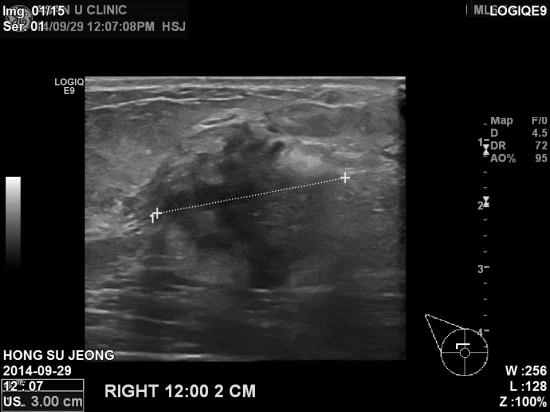

본원 초음파 검사상 우측 유방 12시 방향에

3cm혹과,

겨드랑이 림프절 비대 소견 있어